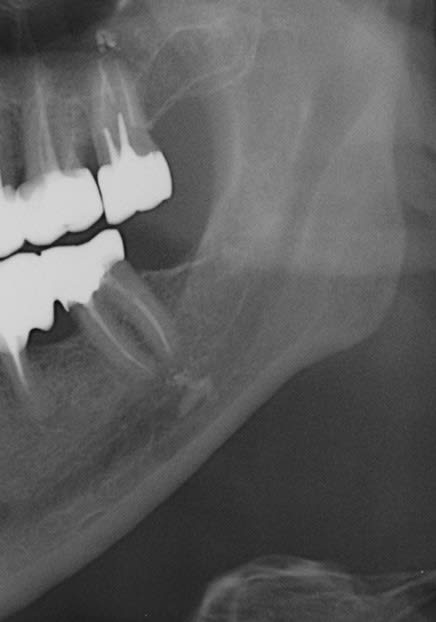

exemple d'endo sous tronculaire...